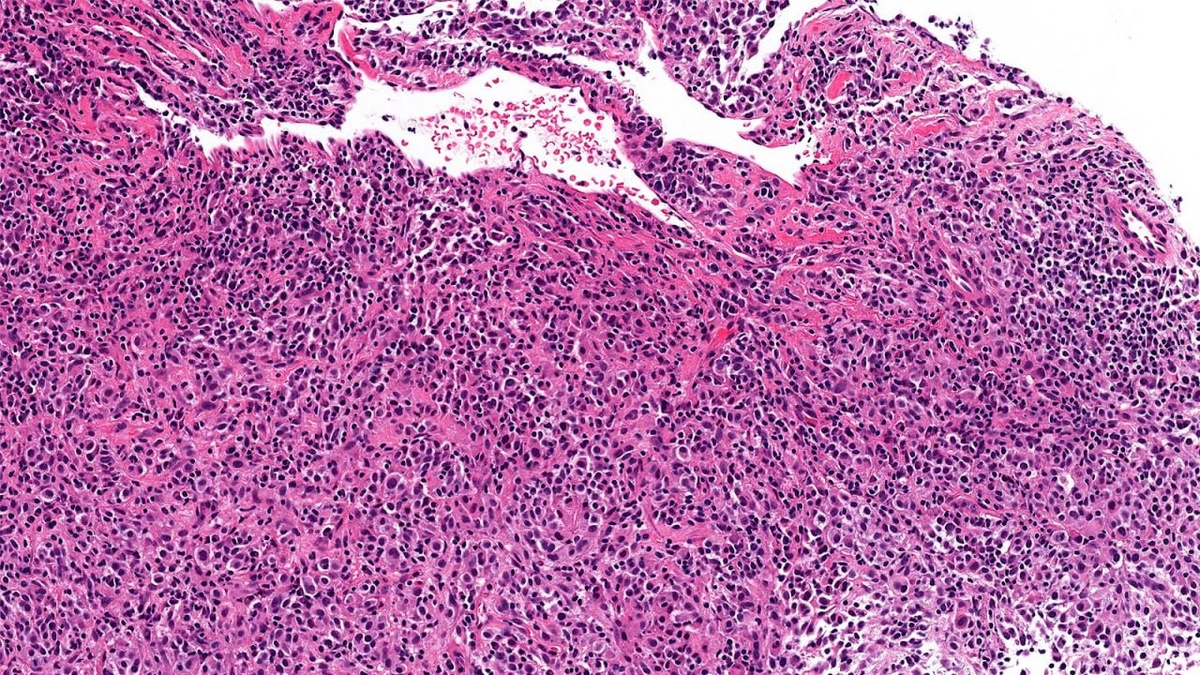

Метастатическая меланома в молочной железе — явление редкое, но вполне возможное.

Как известно, меланома заслуженно носит репутацию «великого имитатора». В данном случае она может приобретать плазмоцитоидную морфологию (как показано на фото) и имитировать картину инвазивной дольковой карциномы.